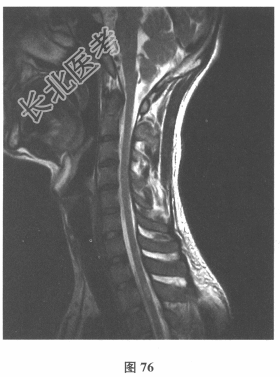

- 简答题3、颅脑MRI:无异常。血清AQP-4抗体(-),脑脊液OB(+),各种自身抗体测定均阴性。VEP:右眼P100潜伏期延长。患者3年前无明显诱因出现双下肢麻木无力,伴有大小便障碍,脊髓MRI显示髓内长T₂信号影,见图76、图77。)此患者的诊断考虑